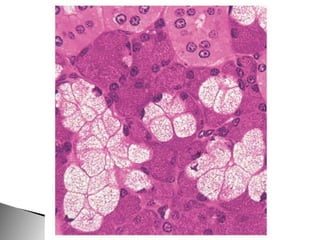

Glándulas alveolares de la próstata, tinción de van Gieson.